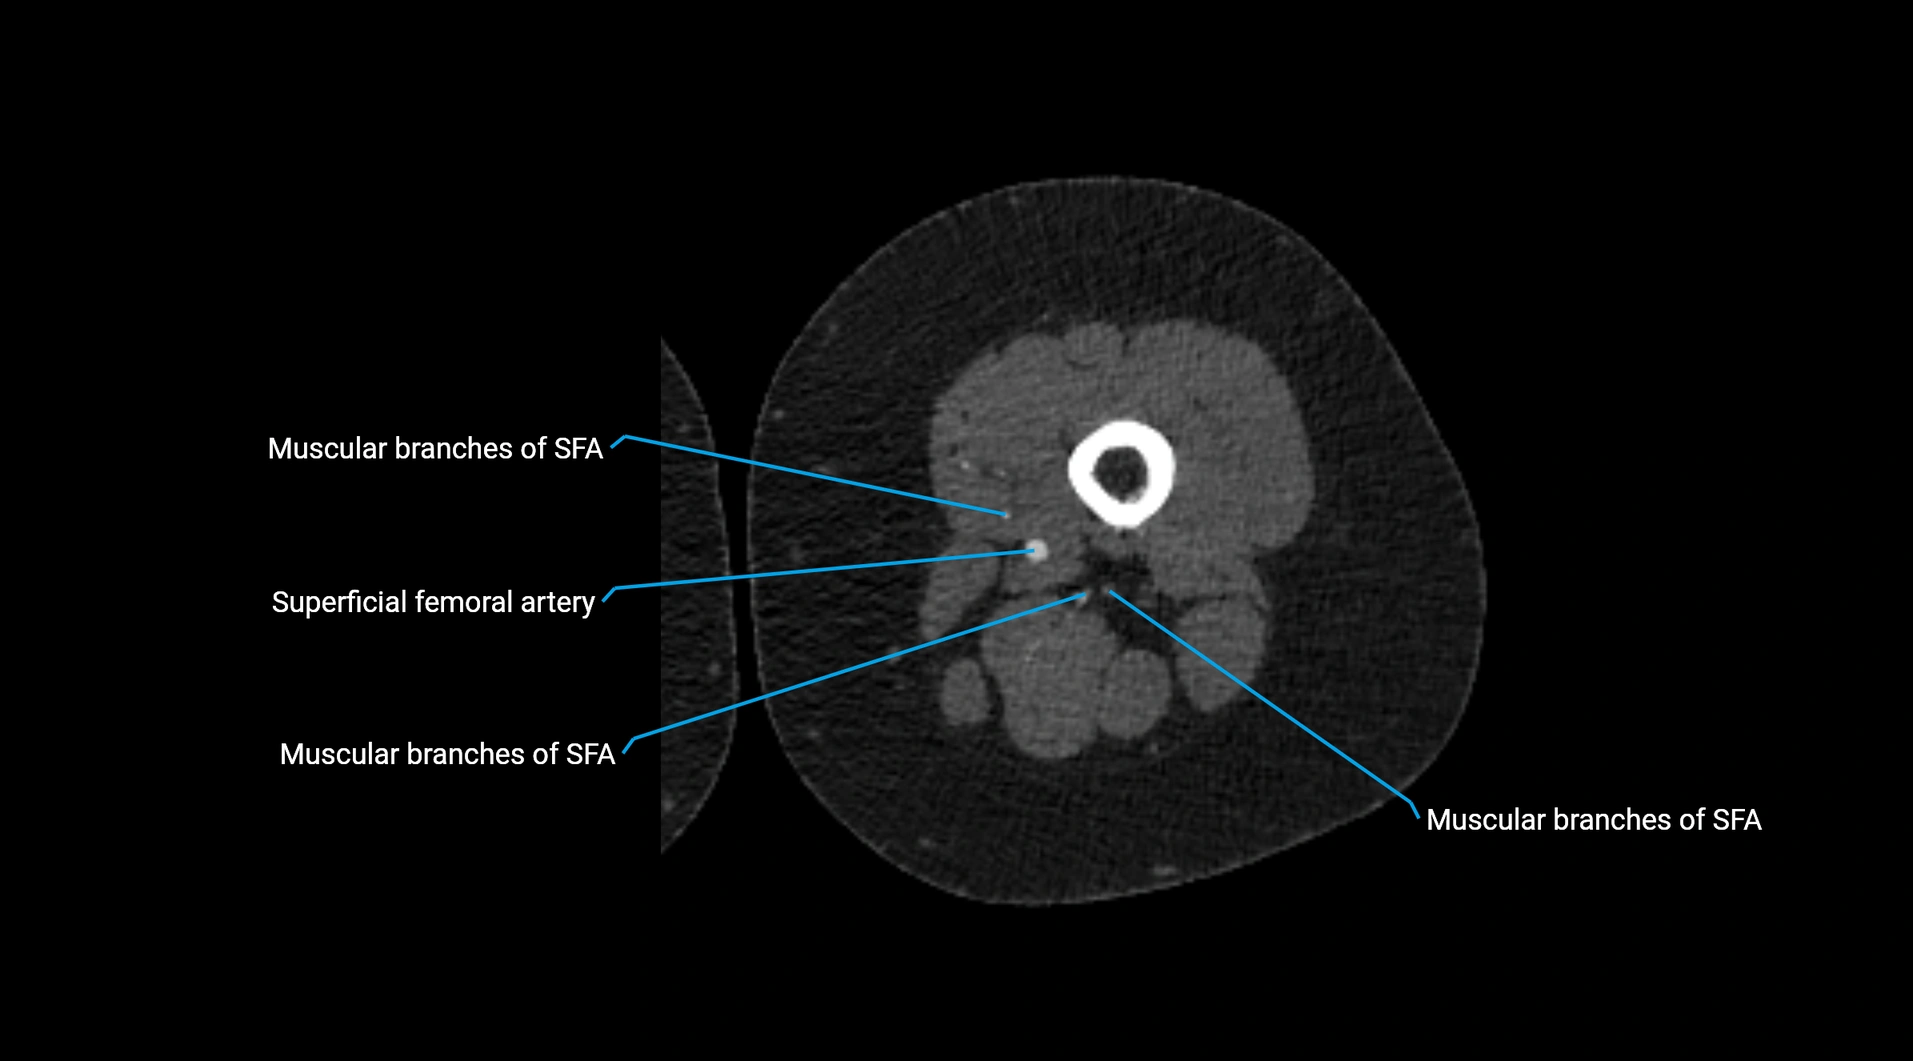

CT images

image